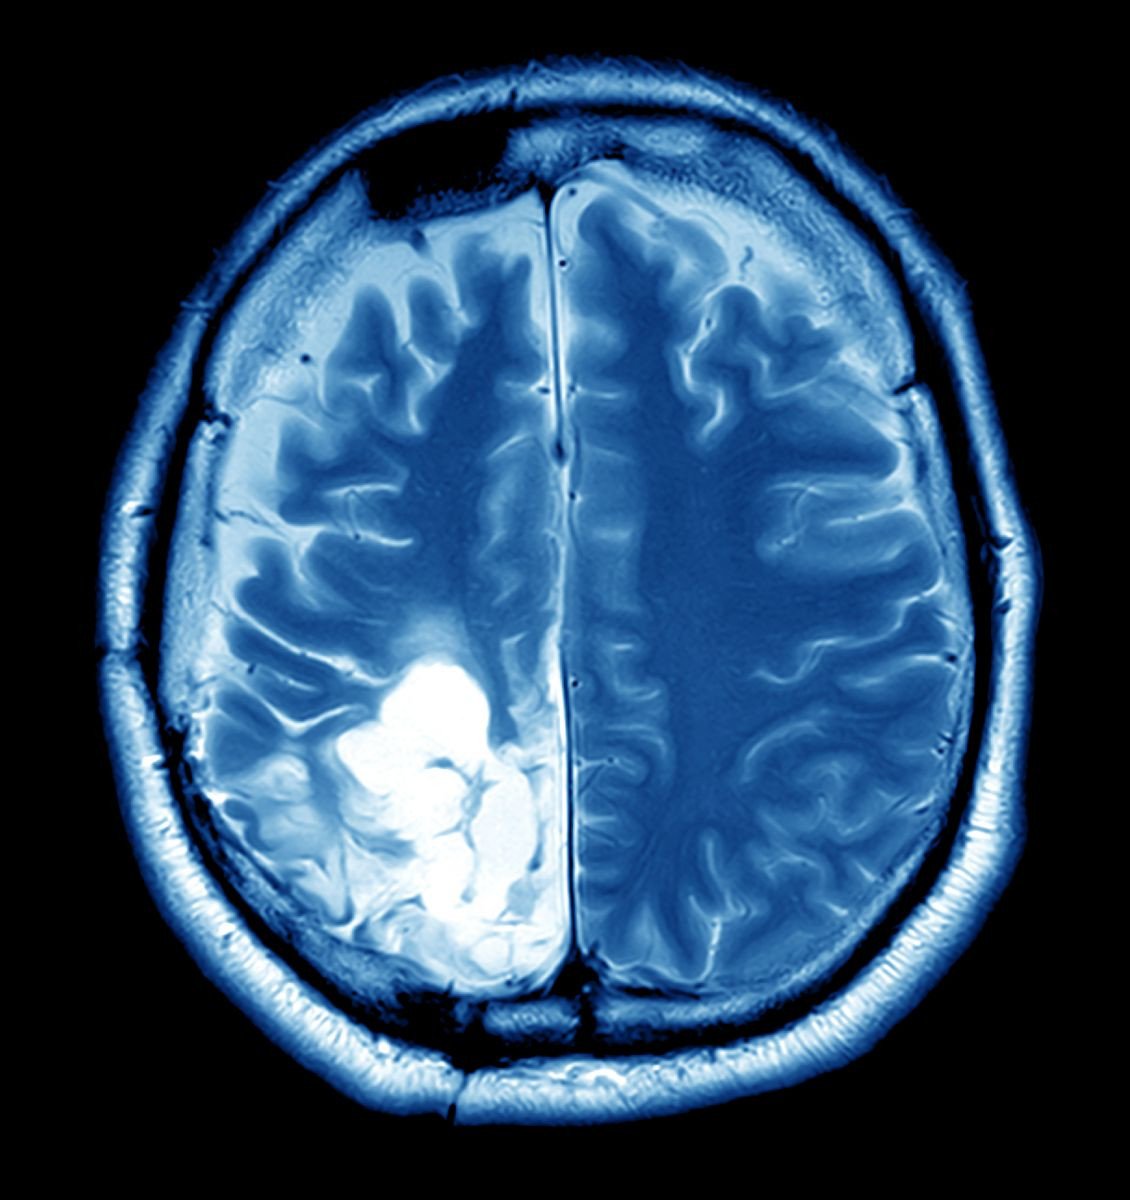

A visit to the doctor revealed the unthinkable – a brain tumor. The diagnosis left Anjali and her family in a state of shock and despair. The emotional turmoil was immense, but Anjali was determined to fight back. It was then that she was referred to Raghav Neuro Trauma Care, a beacon of hope for countless patients like her.

The diagnosis of a brain tumor brings with it not just physical challenges but a significant emotional burden for the patient and their loved ones. The fear of the unknown, the anxiety about the future, and the stress of undergoing a complex surgery can be overwhelming. This emotional turmoil is a major problem faced by many patients, including Anjali.